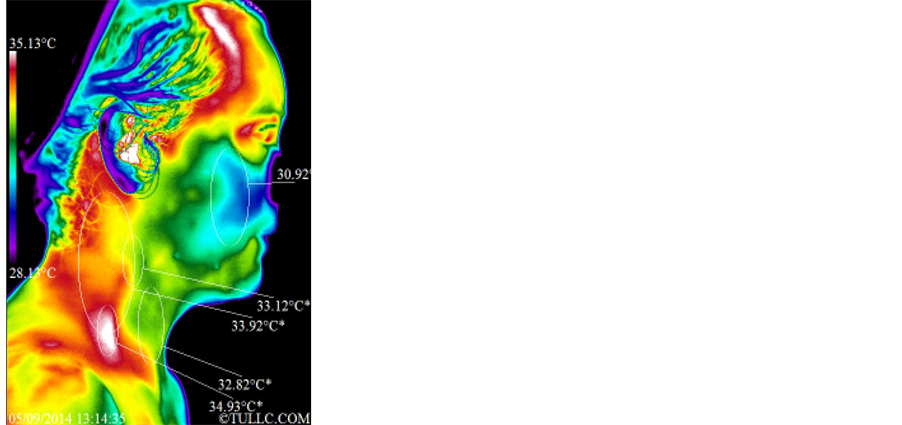

Subject B’s facial thermal images were analyzed using a span of 7.01˚C and positioning between 28.22˚C and 35.23˚C. Figure 7 shows that the temperature of her face decreased significantly (32.54˚C - 31.95˚C = 0.59˚C). Statistical details of the image markers are presented in Table 1. Figure 8 top images show Subject B’s right

lateral views of the face and the images below those show left lateral views of the face before and after the grounding session. The span and positioning is the same as in Figure 7. Both sides of the face clearly cooled off. For example the marker of the right cheek decreased significantly (31.19 ˚C - 30.34˚C = 0.85˚C). Statistical details are presented in Table 2. Figure 9 shows full anterior views of the torso before and after the grounding session. This subject pointed a region of pain on the right side of the right breast near the arm pit, as shown by the circled letter “P” in the before picture of Figure 9. The span and positioning for these images is between 27.54˚C and 34.55˚C. The temperature of the abdomen increased but the temperature around the neck and shoulders decreased. Also the temperature of the right breast decreased while that of the left breast increased bringing them into an improved temperature symmetry. The temperature of the region around the umbilicus increased by exactly 0.5˚C (32.74˚C - 32.24˚C = 0.5˚C). Statistical details are presented in Table 4 and interpretation of patterns in the Discussion section.

the asymmetry. Statistical details of the image markers are presented in Table 1. Figure 11 top images show Subject C’s right lateral side of the face and the images below show her facial left lateral side before and after the grounding session. The span and positioning is the same as in Figure 10. The right lateral side of the face (particularly the cheek) and the anterior neck cooled off while the posterior lateral aspects of her neck became warmer. On the left lateral side, we see a similar pattern i.e. the anterior neck cooled off while the posterior lateral aspects of the neck and the supraclavicular region warmed up. Statistical details are presented in Table 2. Figure 12 shows full anterior views of Subject C’s torso before and after the grounding session. The span and positioning for these images is between 27.77˚C and 34.78˚C. The regions marked with the letter “P” on the left thermal image are regions of pain as pointed out by the subject. The temperature of the torso in general decreased while the temperature of the region around the umbilicus increased but not significantly except for the region immediately above the umbilicus (32.12˚C - 30.87˚C = 1.25˚C). Statistical details are presented in Table 4.

All markers of Figure 4 increased in temperature after the grounding session. This is due to the entire torso surge of lymphatic/venous flow routing lymphatic fluids via the inferior vena cava/right subclavian vein/thoracic duct into the left subclavian vein. The upper torso fluids are also routed to the heart via the superior vena cava. This happened while grounded in order to produce a physiological homeostasis/stabilization of core temperature. This subject had what appears to be a purging of lymphatic/venous congestion that not all subjects experienced. As in Figure 4, all markers of Figure 5 increased in temperature. Significant overall head/neck increased temperatures appear to be related to cranial fluids competing with torso fluids that are being overly dumped into the same veins [14] - [17] .

Subject B has a history of right thumb pain with surgery in the region and right lateral breast region pain of a mild intensity. Figure 7 shows significant drop in temperatures over the forehead/eye/oral regions. These indicate significant improved decongestion of the anterior region of the head/neck and significant drop in inflammatory response over the right lower periodontal disorder. There is significant improvement of the lymphatic drainage thermal marker along the right side of the throat to the sternum. Frequently, while viewing the supraclavicular region, one sees a temporary increase in temperature with the surge of lymphatic/venous fluids to the region, but in this case a significantly improved symmetry to the contralateral region and a drop in actual temperature can be seen. This type of drainage and symmetry indicates a healthier pattern overall. Figure 8 shows a significant drop in temperatures over the temporal and oral regions. These indicate improved temporalis myofascial activity with reduced temporomandibular joint compromising effects. There is also a significant reduction in the sternocliedo hypercontractive state. The external jugular vein is hot due to distension of the vein associated with bilateral scalenus myofascitis causing entrapment and back-pressure on this vein. Looking at Figure 9 the diaphragm/hiatal region of the stomach shows minimal changes, radiating lymphatic/venous congestion along the ascending/descending colon into the lower pelvic floor. There is a significant surge in lymphatic/ venous fluids from the lower extremities. The temperature of the colder areas of the abdomen (related to abdominal pressure) increased and this corresponds to a reduction in distention patterns. Overall temperatures improved from the diaphragm to the clavicle, with significant drop in anterior deltoid temperature and improved symmetry of the breasts.

Subject C has a history of 2 fibroid in the uterus with intermittent lower pelvic pain ranging from 2 - 4, also right lower pelvic region. Figure 10 shows significant drop in temperatures over the following regions: forehead/eyes/orbit/surrounding nasal and oral regions. This is indicative of decongestion of the lymphatic/venous system of the head/neck with reduction in histamine type thermal markers surrounding the eyes and mouth. There is a significant reduction in periodontal inflammatory thermal markers that include the submandibular lymphatic system. The forehead heat pattern appears related to occiput/atlas entrapment of the suboccipital nerve/ vertebral artery resulting in dural influences affecting the 5th cranial nerve, thus causing frontalis/temporalis hypercontraction. In Figure 11, Subject C’s temporalis and temporal mandibular joint had improvement in myofascial activity and reduction in joint compromising effects on both laterals. Yet, increased posterior neck temperatures appear as if this subject was influenced by the elevation of the pillow and headrest of the reclining chair. Significant drops in temperature over salivary gland sites, while the external jugular vein and the scalene region demonstrated consistent temperatures on the pre-post study. The images of the full anterior views of the torso shown in Figure 12 presented a drop in temperatures over the acromioclavicular joints, around the clavicles, much of the spotted breast fibrocystic activity, significant drop in lymphatic/venous congestion heat pattern surrounding both nipple and areola, specially on the right side, and temperature decreases in lymphatic/ venous congestion below the breast. However, the hiatal region over the stomach had only a small drop in temperature, while small intestine and lower pelvic thermal markers increased by more than 1˚C with changes in abdominal distension pattern. Abdomen changes in pattern, like those observed around the umbilicus for this subject, are indicative of treatment/intervention effects (grounding). Autonomic control, or the lack there of, tends to produce consistent markers and patterns in the same geographical regions. Significant increased in vascular fluidity /digestive fluids/cerebral spinal fluid with improved autonomic control is related to intestinal lining motility. Clinical observations over the years have shown repeatedly that these changes in pattern do not happen without an external intervention.